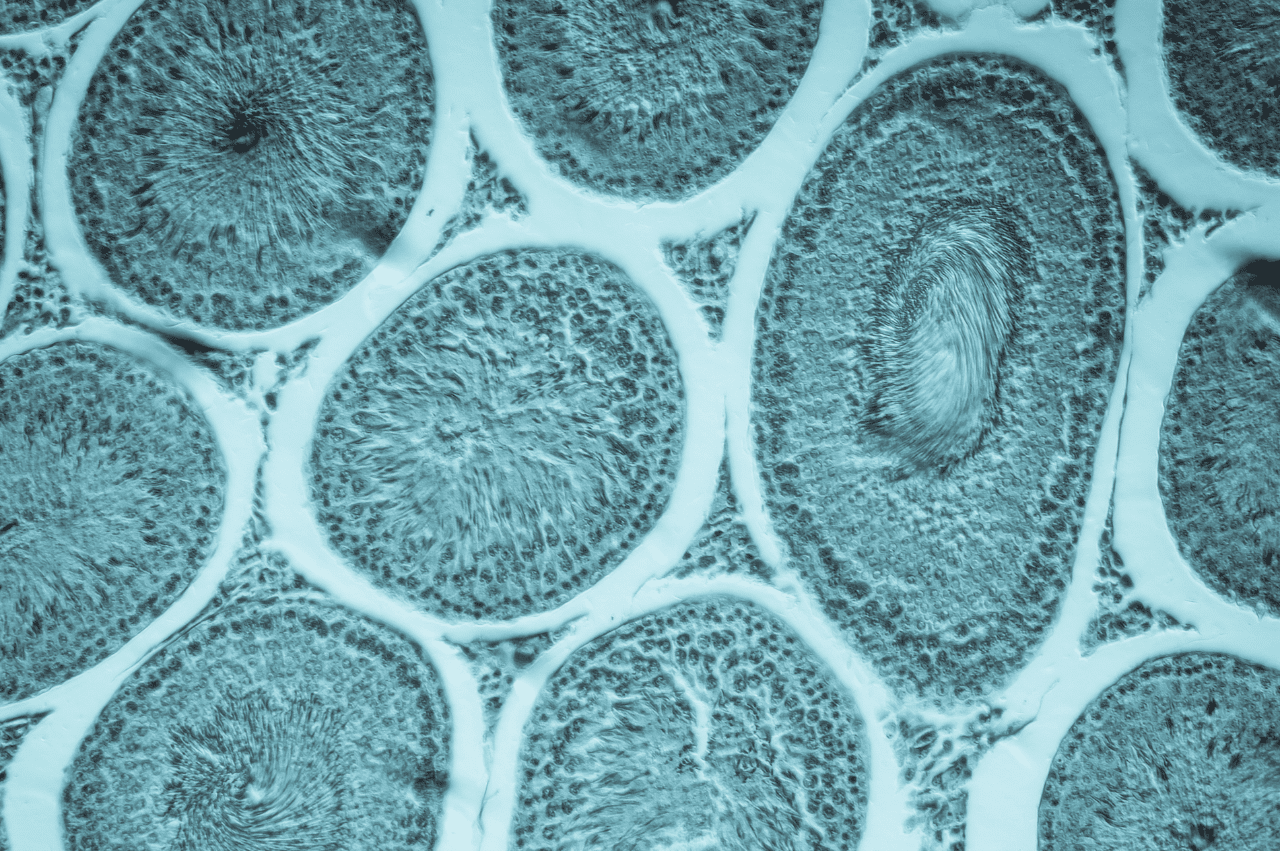

- Day 1-5: Your ovaries begin responding to the medications, growing multiple follicles simultaneously. Each follicle contains an egg. You’ll start regular monitoring appointments to track your progress.

- Ultrasounds show how many follicles are growing and their size. These transvaginal ultrasounds are quick and help your doctor determine when you’re ready for egg retrieval.